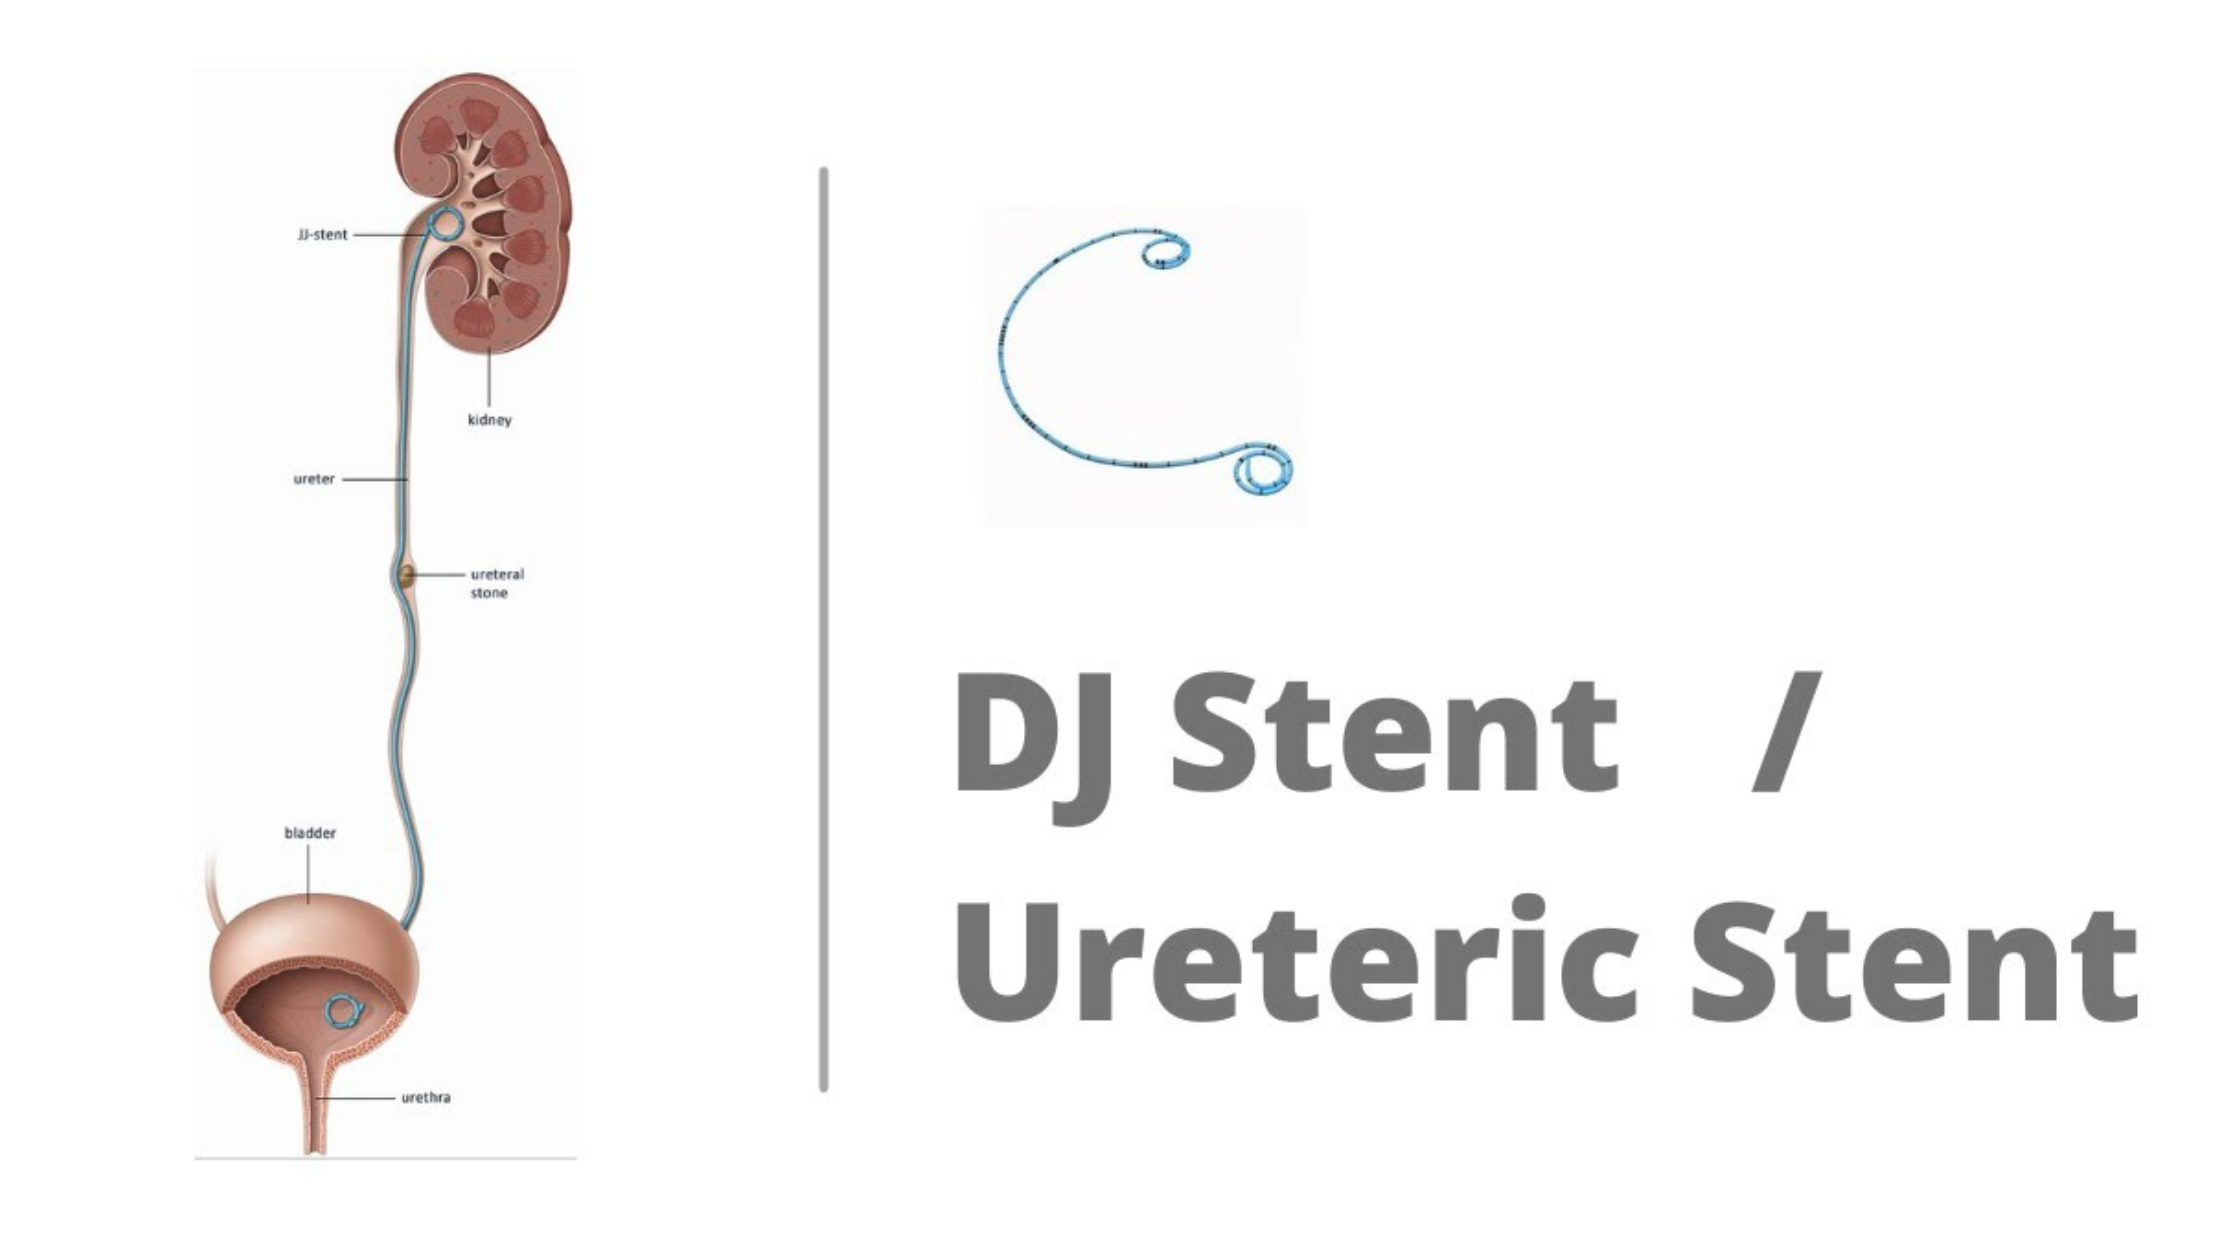

DJ Stent for Kidney Stones

Kidney stones can bring about excruciating pain and discomfort, affecting millions of individuals globally. When these stubborn stones refuse to pass naturally or grow too large to be managed with […]